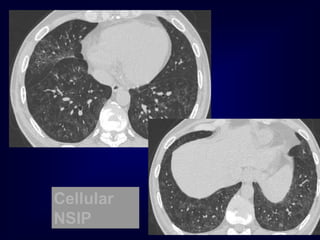

DI

P

Cellular

NSIP